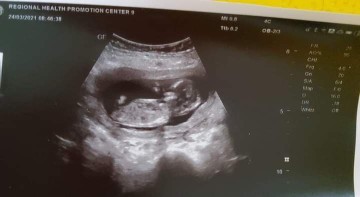

10+3ตอนนี้12